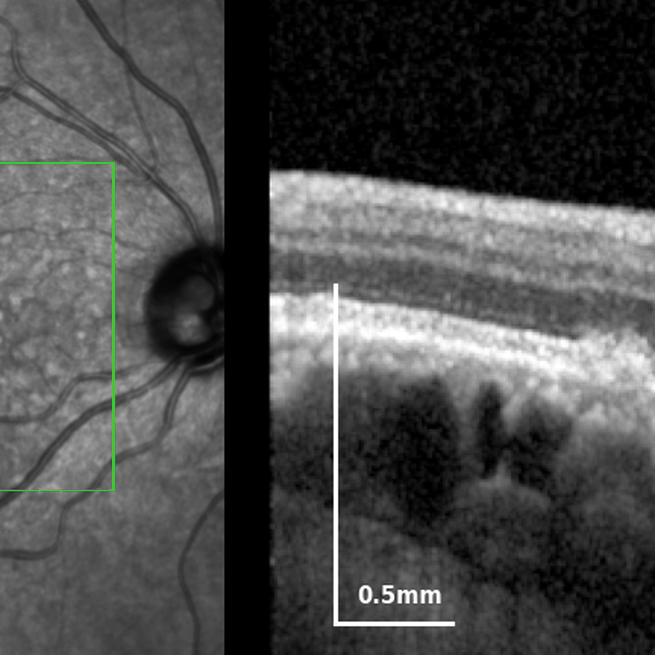

A python package to read, analyse and visualize OCT and fundus data from various sources.

EyeLab is a multimodal annotation tool (GUI) for ophthalmological imaging data.